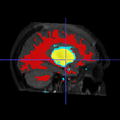

Image:Seg_P4_followup_result_3D_leftview_sp.png|Segmentation result of a new subject - 3D view

Image:Seg_P4_followup_result_3D_topview_sp.png|Segmentation result of a new subject - 3D view